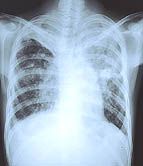

It is common for internationally adopted children to have latent tuberculosis infection and to have an initial false negative result from a tuberculin skin test, according to a report published in the July issue of Pediatrics.

Latent tuberculosis infection was initially detected in 111 (21 percent) of the children, and 191 children (46.9 percent) of those initially with a negative skin test were re-tested. Of these, 20 percent had latent tuberculosis, but none had active tuberculosis disease.